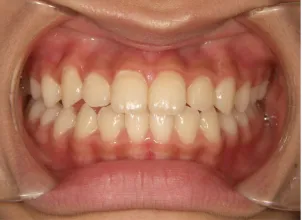

治療前①小2:8y1m 初診

| カウンセリング・診断結果 | 前歯が受け口になっていているため、適正な成長へ誘導するために前歯の咬み合わせの改善が必要なことを説明し、診断を希望されたので精密検査へ進みました。 精密検査の結果、骨格的には受け口傾向、下顎前歯の突出、上下ともアーチが小さく凸凹(叢生)が認められ、機能的には低位舌と口唇閉鎖不全があり、口元は上下唇とも突出していますがコンケーブになってないことがわかりました。 |